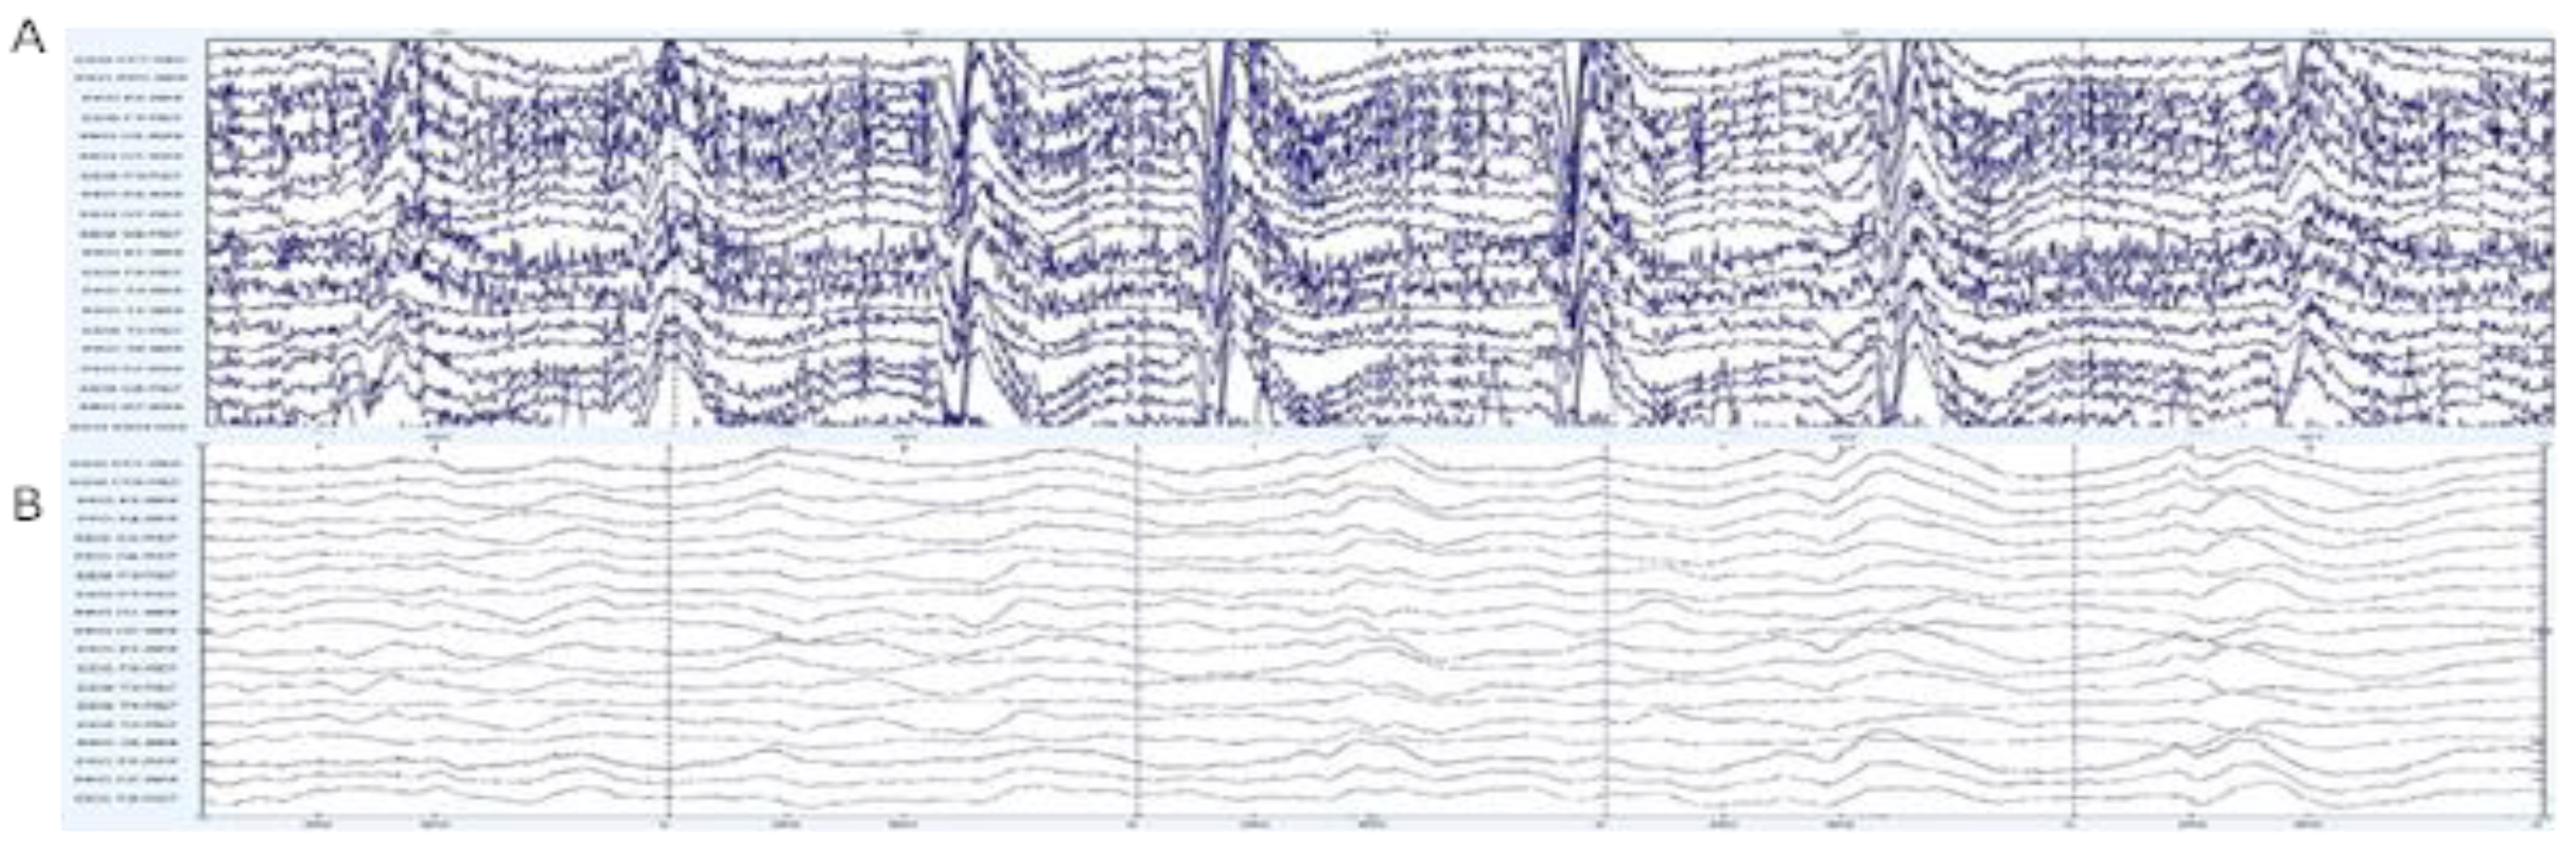

2.2.1. Pre-Processing